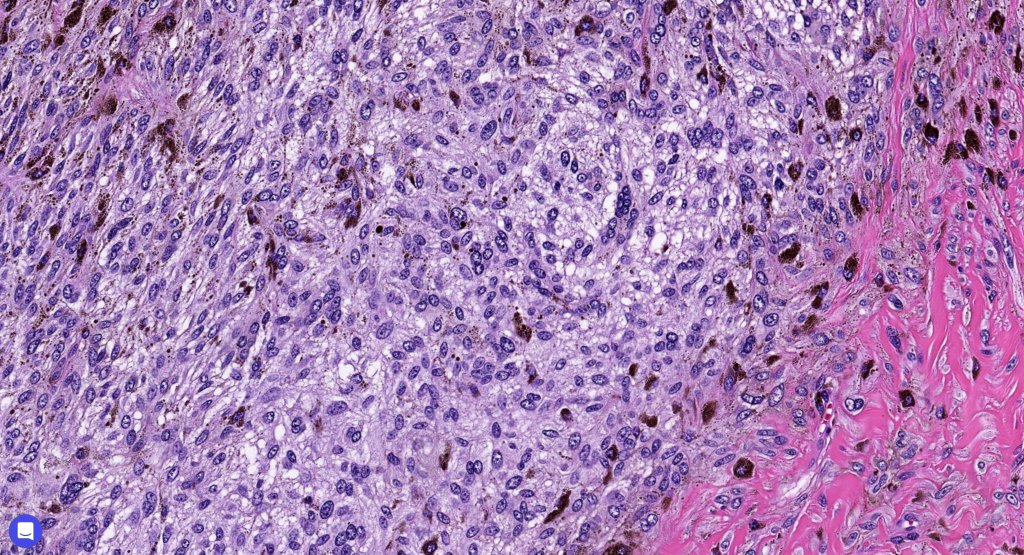

•Admixture of spindle cells, pigmented bipolar or dendritic cells & melanophages

•Cytoplasm is pale and nuclei are small with inconspicuous nucleoli

•An alveolar pattern is characteristic particularly with clear cell nodules

•Mitoses are typically very sparse or absent

•No atypical mitoses

•No Necrosis or lymphovascular invasion

•Multinucleate giant cells sometimes present

Atpical blue nevus

This is exceedingly rare and the diagnosis should be used very sparingly. It is likely quite benign although very occasionally, a sentinel node biopsy is positive. Great care must be taken to make sure that a blue nevus-like melanoma isn’t missed. It shows the low power features of a blue nevus but high power scrutiny reaveals pleomorphism, nuclear hyperchromatism and increased mitotic activiy (<1 sq mm). Abnormal mitoses are absent as is necrosis. Perineural involvement can be seen but lymphovascular invasion is absent.